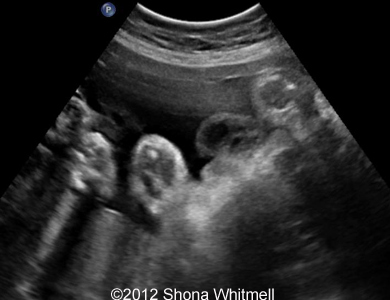

Figure 1: 3-vessel cord at the fetal end

Image-18